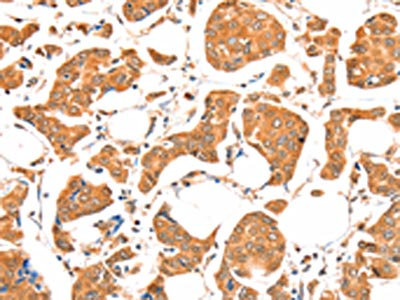

The image on the left is immunohistochemistry of paraffin-embedded Human breast cancer tissue using CSB-PA383927(ACSM5 Antibody) at dilution 1/20, on the right is treated with fusion protein. (Original magnification: ×200)

The image on the left is immunohistochemistry of paraffin-embedded Human colon cancer tissue using CSB-PA383927(ACSM5 Antibody) at dilution 1/20, on the right is treated with fusion protein. (Original magnification: ×200)